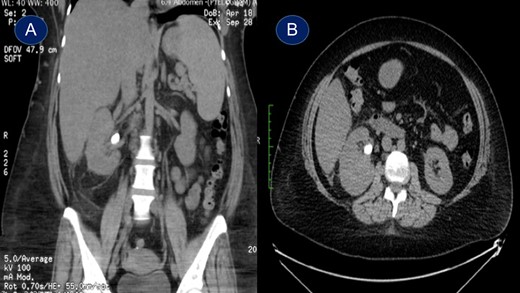

This is a 45-year-old female patient known to have diabetes mellitus and old cerebrovascular attack presented with right flank pain. Laboratory investigations revealed normal WBC count with a hemoglobin 10.4 mg/l. Radiological investigation showed right a 20 mm right renal stone (Fig. 1). Patient underwent FURS-L using a 10/12Fr Ureteral Access sheath. We did endoscopic renal exploration plus laser lithotripsy using Flex-Xc STORZ. The irrigation was under hydrostatic pressure of 80 cm H2O. The procedure was uneventful with an operative duration of 88 minutes. However, severe extravasation was noted at the end (Fig. 2). Six hours postoperatively the patient started to have high grade fever with a sudden drop of hemoglobin level to 6.6 mg/l. Immediate abdominopelvic CT scan with contrast was carried out showing severe right subcapsular renal hematoma. This complication was managed conservatively through proper antibiotics, blood transfusion and good hydration for 7 days. The patient was seen in the outpatient clinic 2 months later with a new abdominopelvic CT scan which showed a regression of subcapsular renal hematoma and surprisingly migration of stone fragments into the regressed subcapsular hematoma (Fig. 3). On the other hand, the upper urinary tract was free of stones.

Plain abdominopelvic CT scan, coronal view (A) and axial view (B) showing right renal pelvic stone measuring 20 mm.